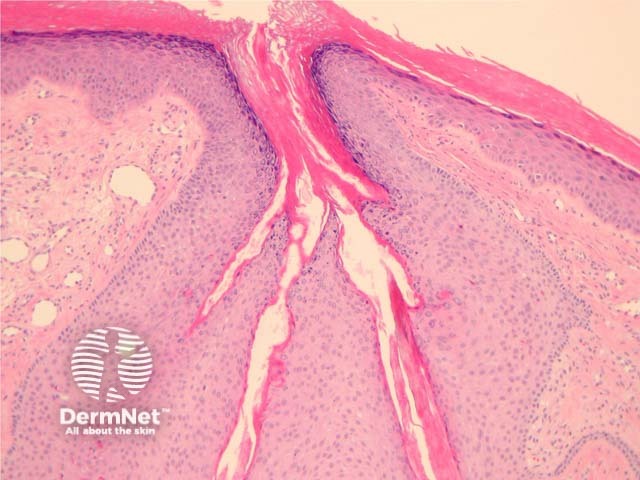

In trichofolliculoma, sections show numerous small follicles radiating from a central larger follicle. The hairs are surrounded by a well circumscribed dense stroma. (figures 1–3). The surrounding hairs are generally very small (vellus). Intermixed Merkel cells and sebocytes may be seen. A sebaceous variant has been described (sebaceous trichofolliculoma).

Figure 1